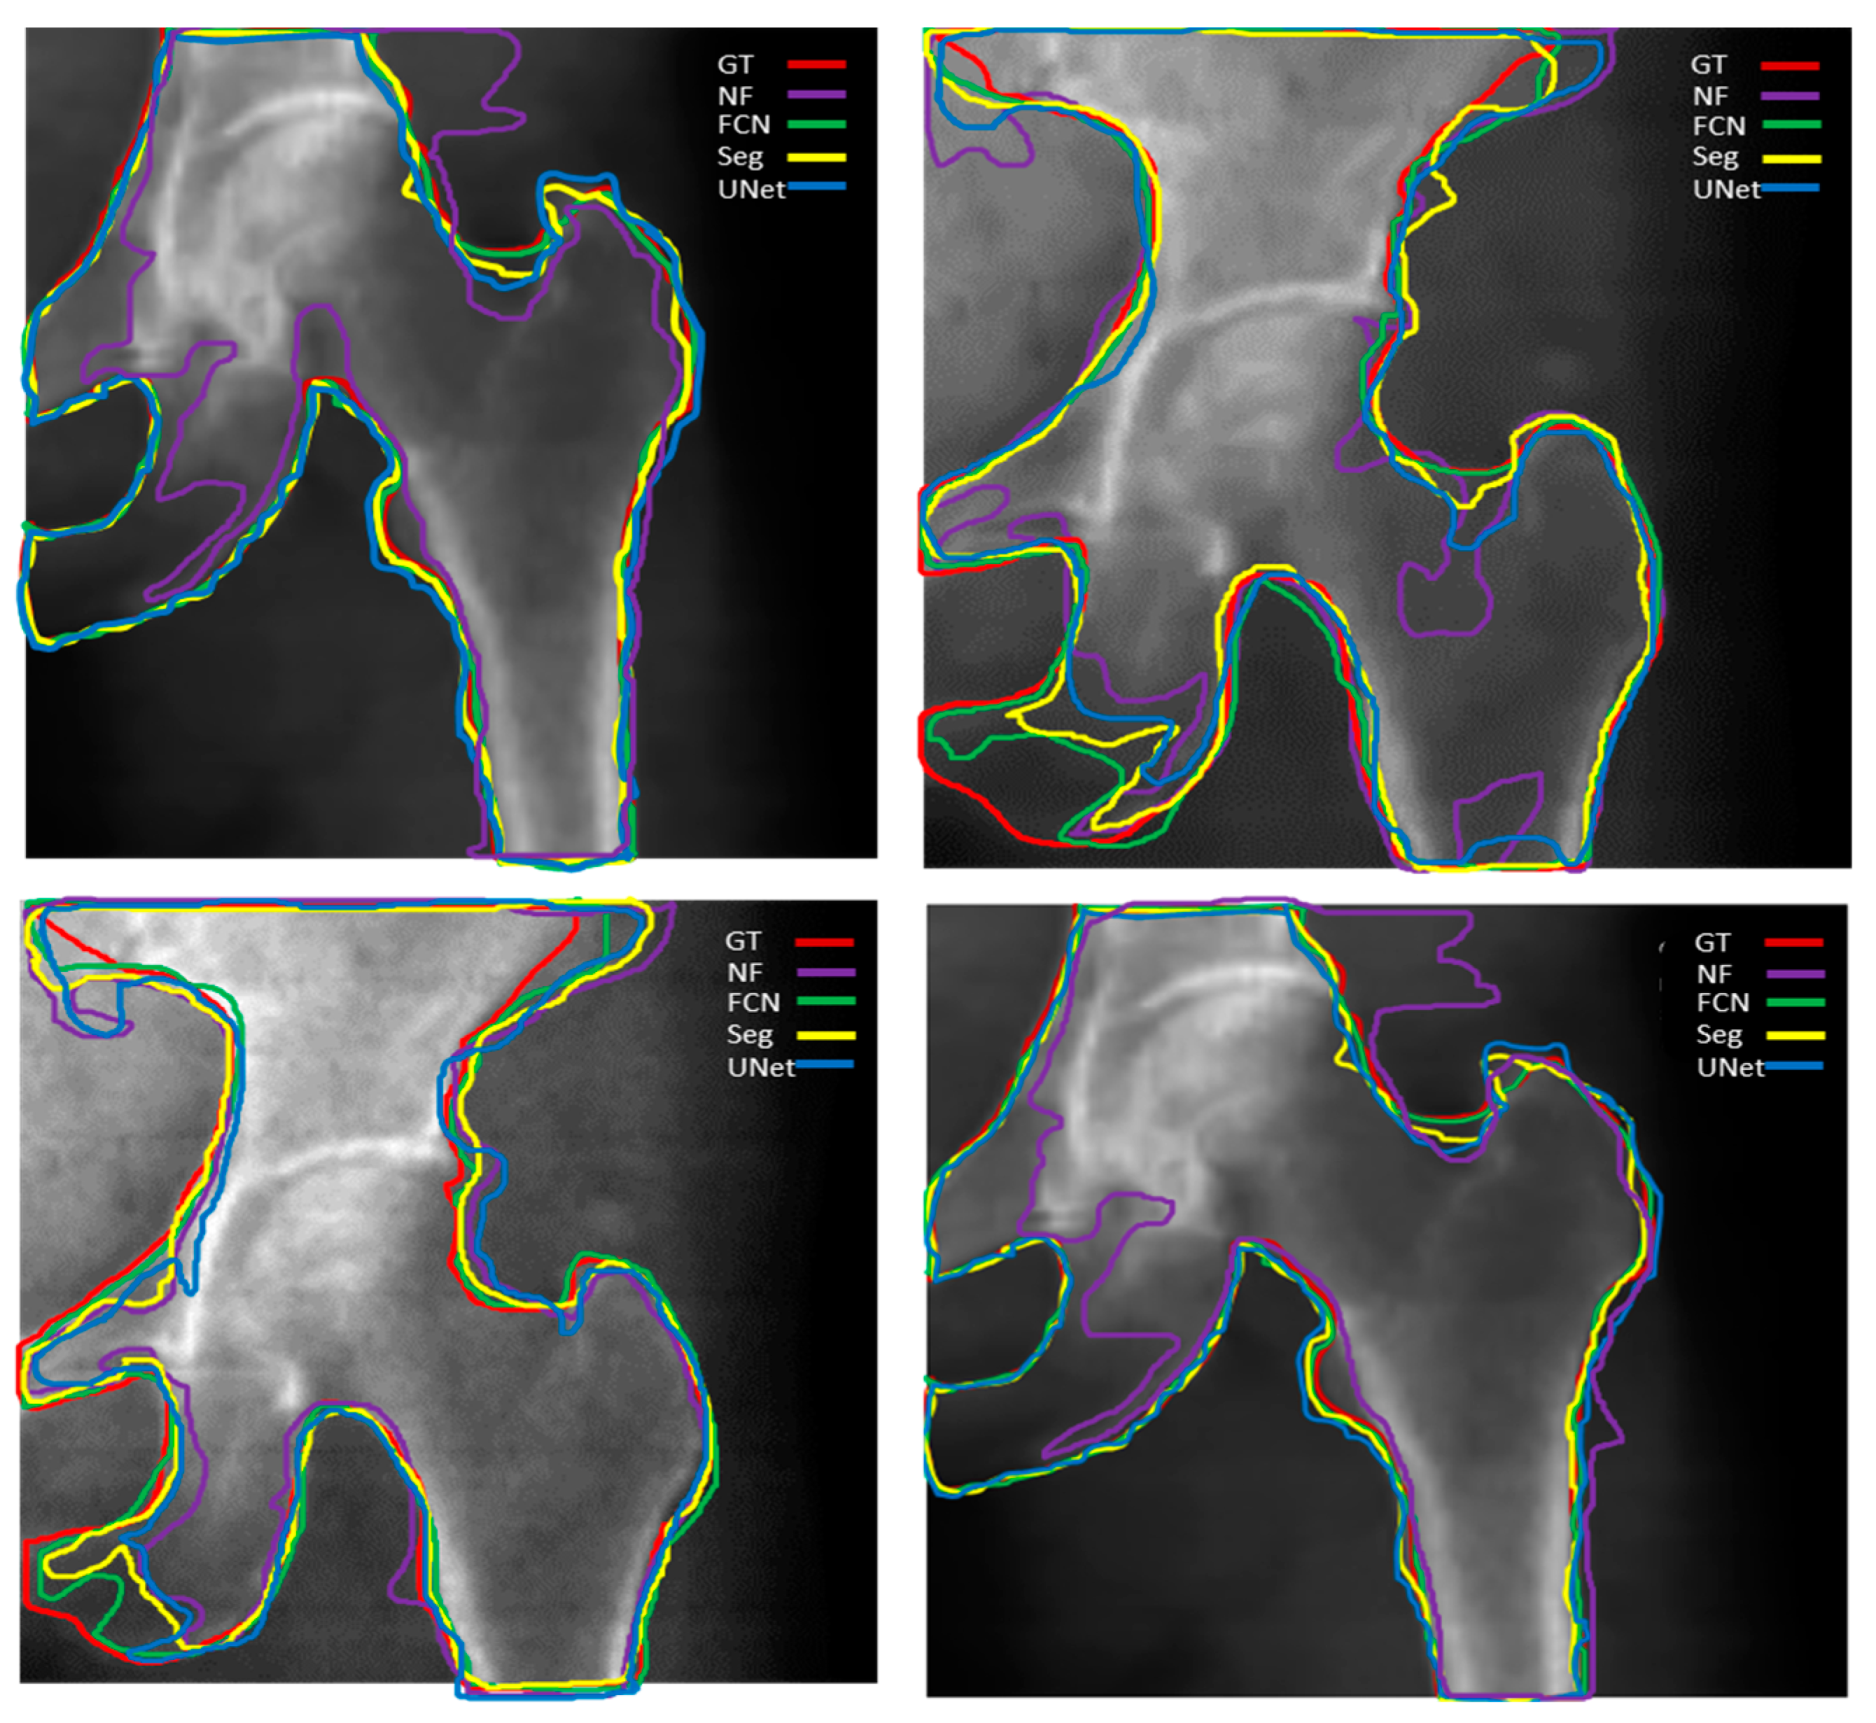

This section presents the performance of U-Net, SegNet, and FCN approaches using test data (i.e., 250 femur images). Some of the selected results from U-Net, SegNet, and FCN output with non-smooth contours, and binary smoothed contours are shown in Figure 6 and Figure 7, respectively. Figure 6 presents the raw output of DL models without any additional post-processing applied. This means that the segmentation results shown in Figure 6 are directly generated by the DL algorithms (SegNet, U-Net, and FCN) without any further enhancement or adjustment.

In contrast, Figure 7 illustrates the results of the same DL models after applying a binary smoothing filter as post-processing. The binary smoothing filter is applied to the segmentation masks obtained from the DL models to refine and smooth out the boundaries and contours of the segmented regions. This post-processing step aims to improve the visual clarity and accuracy of the segmentation results by reducing pixel-level noise and inconsistencies in the DL outputs.

Thus, Figure 7 provides a comparison to Figure 6 by demonstrating how the application of a binary smoothing filter can potentially enhance the segmentation outcomes produced by the DL models, particularly in terms of achieving smoother and more coherent boundaries for the identified regions of interest. Table 2 shows the segmentation performance results in terms of average accuracy computed using the JI, sensitivity, and specificity of all test images. In addition, the average Dice score was calculated for bone, soft tissue, and air region in each image, and finally, a combined average Dice score for overall test data of each segmentation model was calculated. A couple of the predicted segmentation contours by different segmentation models using NLMF are shown in Figure 8.

Figure 6. Selected results of two cases segmented with SegNet, U-Net, and FCN without smoothing filters. In this figure, (a1,a2) are the original images, while (b1,b2) represent the ground truths. (c1) on left side and (c2) on right side depict the segmentation masks of the original images (a1,a2) segmented using various DL algorithms without any post-processing applied. These two images were acquired using two distinct DXA imaging devices. The blue arrows indicate air labels in the images.

Figure 7. A binary smoothing filter was applied to the DL output in Figure 6. The results depict two cases segmented using SegNet, U-Net, and FCN with the addition of a binary smoothing filter as post-processing. In this figure, (a1) on the left side shows the segmentation mask corresponding to a1 in Figure 6, while (a2) on the right side displays the segmentation mask corresponding to (a2) in Figure 6. These masks were generated using various DL algorithms (U-Net, SegNet, and FCN, each labeled accordingly) and then smoothed with a binary smoothing filter. The blue arrows indicate air labels in the images.

Figure 8. Predicted femur boundaries using SegNet, U-Net, and FCN segmentation models. Ground truth femur boundaries are outlined in red, while the predicted boundaries are represented by yellow (SegNet), blue (U-Net), green (FCN), and purple (FCN with no filter). The above segmentation results were obtained following a preprocessing with NLMF.